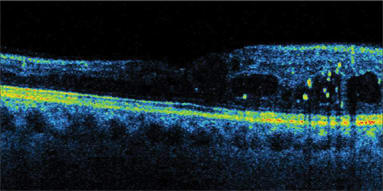

SDOCT does not skip or miss data points, as time domain OCT does because of its speed limitations. Thickness data between time domain scan lines is not actually measured, and values must be interpolated. No interpolation is needed with SDOCT. "We can see pathology that time domain OCT would have missed," Dr. Sharma says. "For example, SDOCT detects drusen or areas of subretinal fluid (Figure 1) that would have fallen between scans on time domain OCT. Also, it is much easier to discriminate pathology with SDOCT technology. For example, it is easier to discern the presence or absence of epiretinal membranes." (Figure 2)

Figure 1. The Copernicus' spectral domain optical coherence tomography maps wet AMD with PED subretinal fluid.